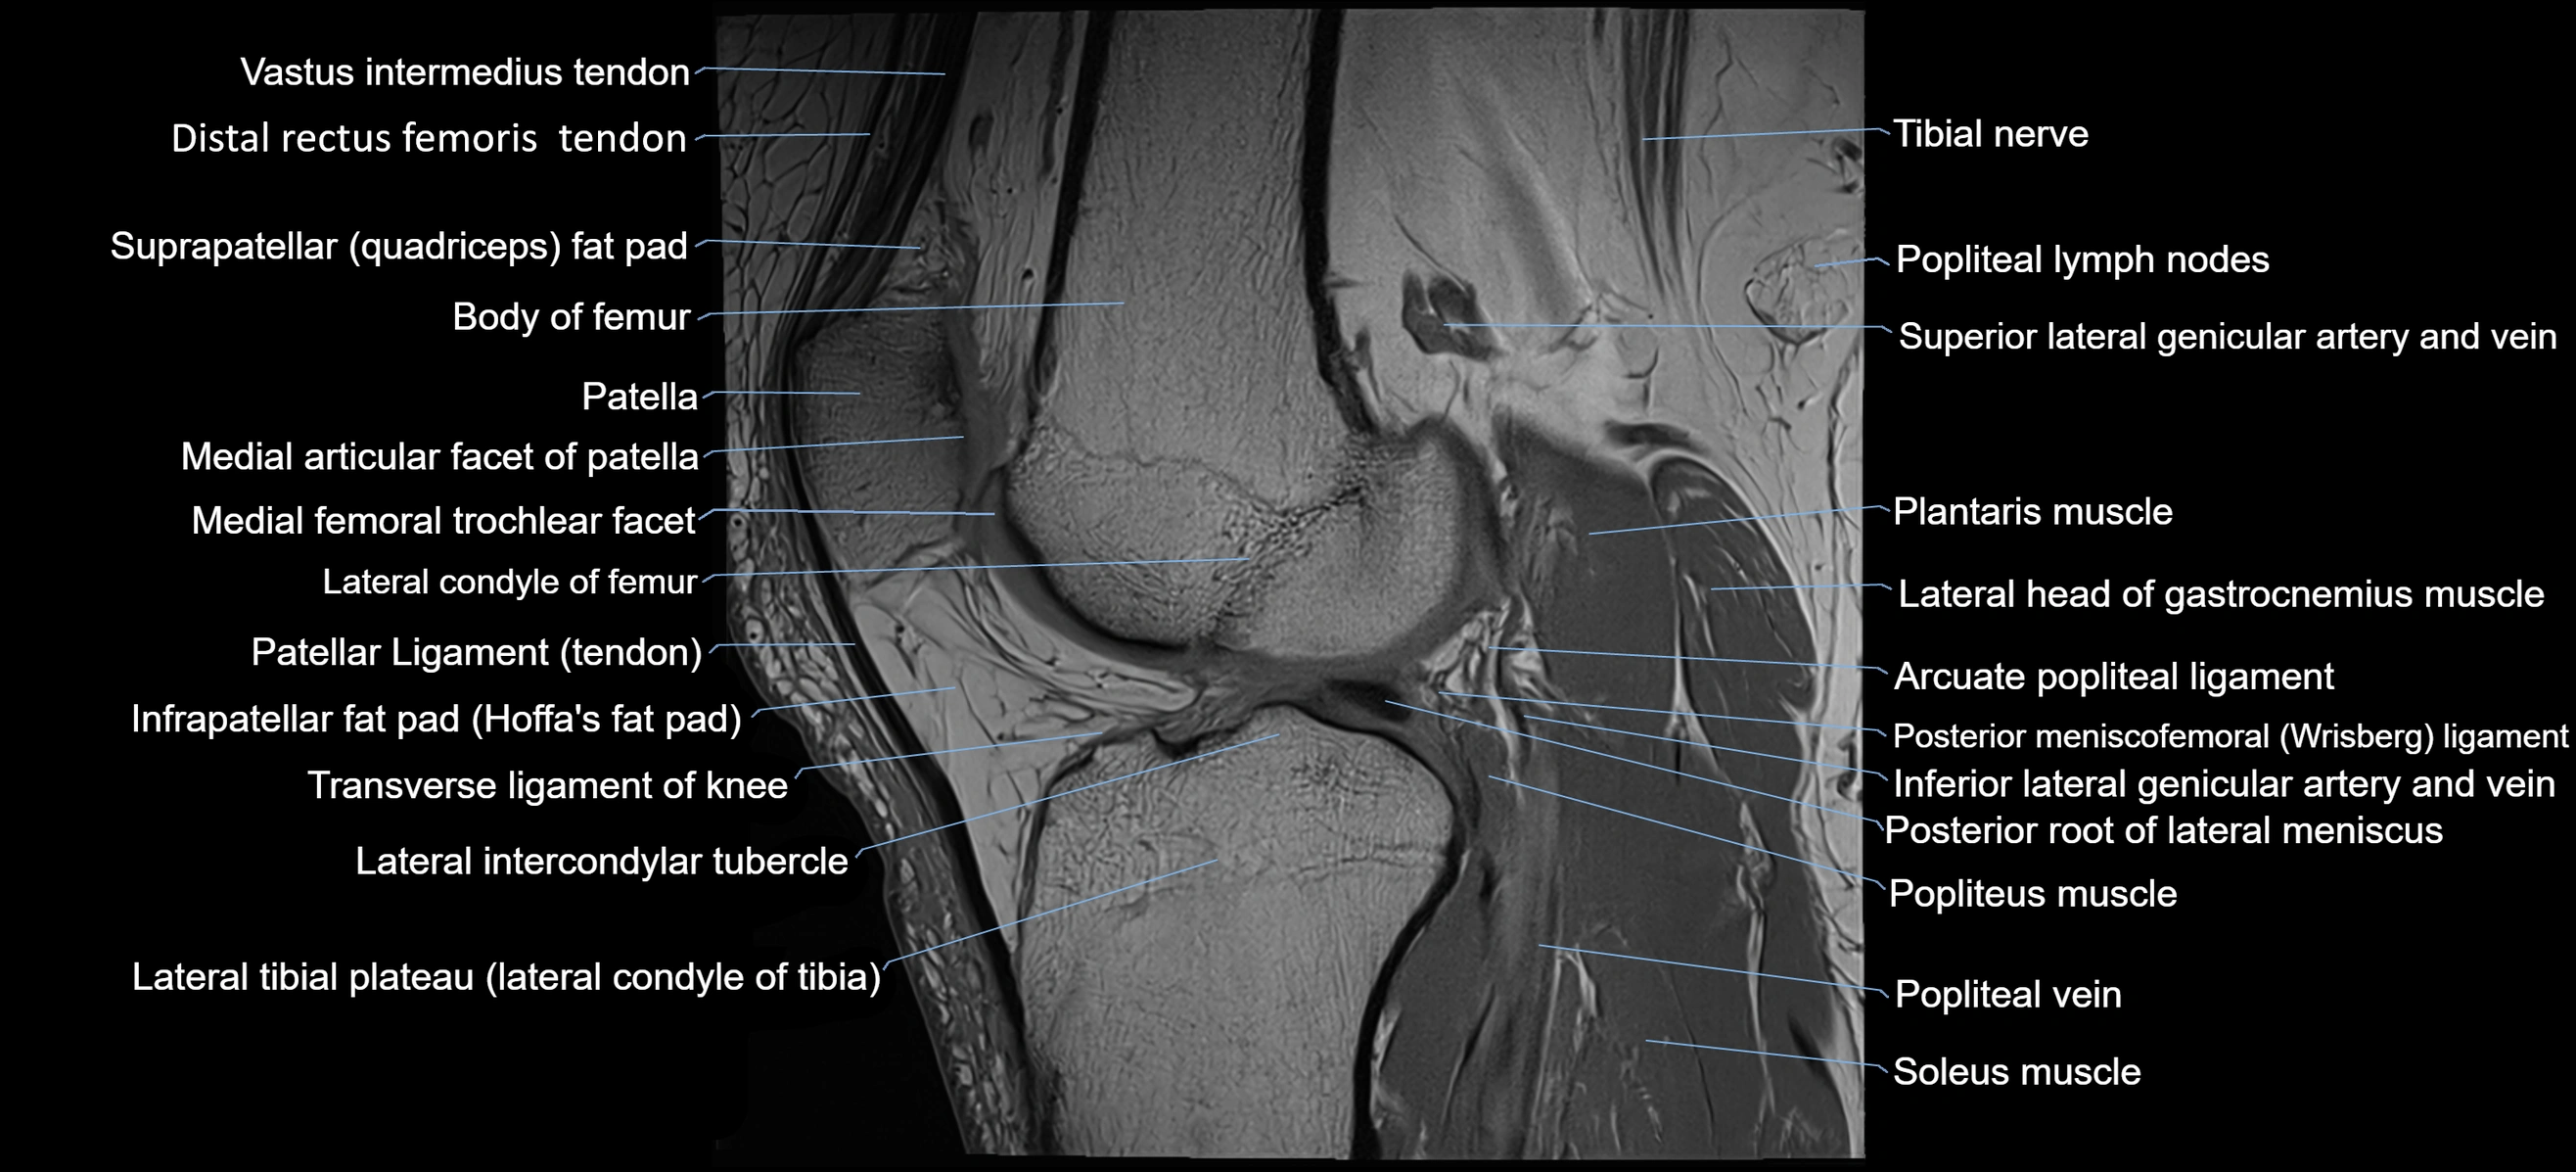

- Arcuate popliteal ligament

- Distal rectus femoris tendon

- Distal vastus intermedius tendon

- Infrapatellar fat pad

- Lateral head of gastrocnemius muscle

- Lateral intercondylar tubercle

- Lateral tibial plateau

- Patella

- Patellar articular cartilage

- Patellar tendon (patellar ligament)

- Plantaris muscle

- Popliteal lymph nodes

- Popliteal vein

- Popliteus muscle

- Posterior meniscofemoral ligament

- Posterior root of lateral meniscus

- Soleus muscle

- Superior lateral genicular artery

- Superior lateral genicular vein

- Suprapatellar fat pad

- Transverse ligament of knee